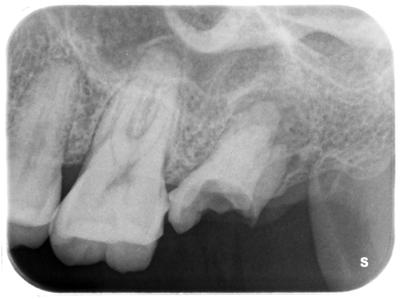

虫歯の進行酷く、根尖に大きな骨吸収、サイナストラクトの形成、多量の軟化質、破折も起こしている。

どこかの医院で治療開始しているようだが、仮封すら何もない。

もっと早く対応していたなら、また、対応可能な歯科医院を受診していたならどうにかなったかもしれないが、このような状況で1年間・・・・・もはやどうにもならない。